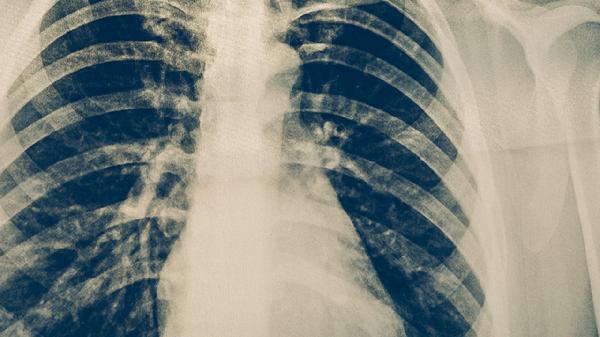

疼痛程度与呼吸深度呈正相关,深吸气时尤为明显,提示可能存在胸腔积液或肺实变。患者常出现浅快呼吸以减轻疼痛,但可能导致缺氧。需通过胸片评估肺部病变范围,必要时行胸腔穿刺引流。